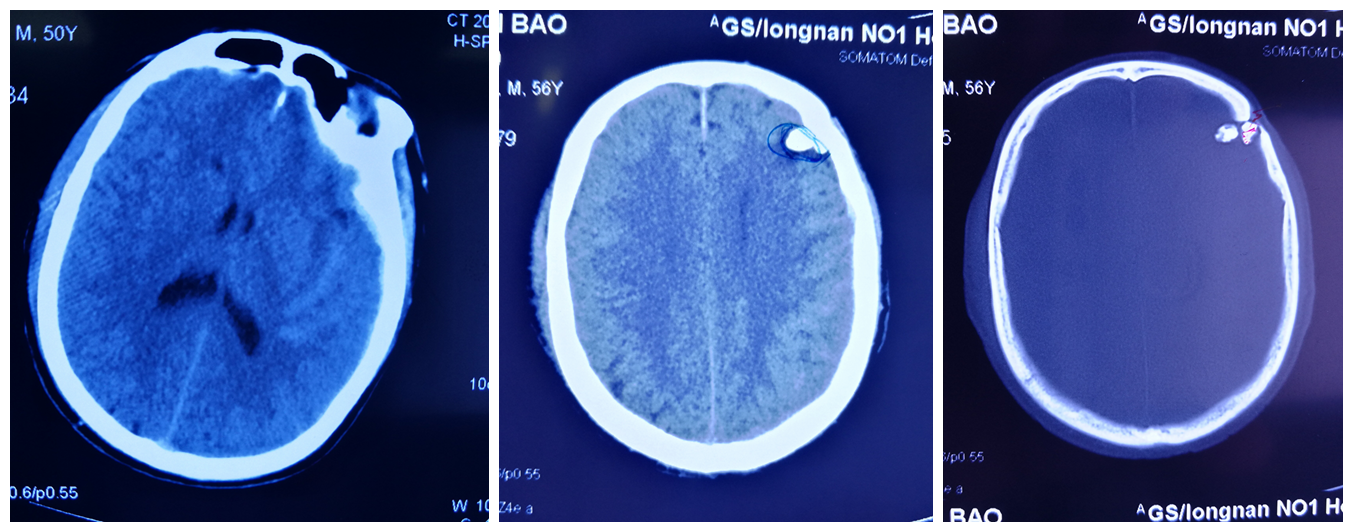

患者56岁,因“重度颅脑损伤;左侧额颞部急性硬膜下血肿;左侧额颞骨粉碎性、凹陷性骨折”收住我院,入院时呈浅昏迷状,GCS评分8分。

入院后,科室副主任周小荔查看患者病情、询问病史得知患者于20年前在开山放“石炮”时头部曾被石头砸伤过,头部伤口自行愈合就没有前往医院治疗。 周副主任行相关检查后,立即带领医师张旭东行手术治疗,术中发现“左侧额颞骨粉碎性、凹陷性骨折”系陈旧伤,开颅血肿清除过程中一并取除刺入颅内的凹陷骨折碎片,令人吃惊的是发现颅内居然有一“黑色”石块,大小约0.4cm×0.5cm,周副主任立即将石块取出,取除石块后反复消毒术区,还纳骨瓣,术后未发生颅内感染,目前患者恢复良好。

此次手术的成功开展不仅清除了颅内血肿挽救了生命,还取除了存留于颅内长达20年之久的异物,一次性解决了患者后顾之忧,减少了癫痫发生的概率,减轻了患者的痛苦。一面锦旗传递的不仅是患者的感谢之情,更是对医院服务品质的认可,对医护人员工作的充分肯定。